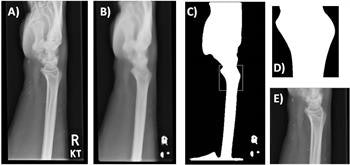

Template matching. The original image (A) is preprocessed using a smoothing algorithm (B), followed by binary thresholding and matching of the template (D) to the most similar region of the preprocessed image (C, white box). The final outcome is shown in (E).

The region of interest was defined using the Python OpenCV matchTemplate function.

"The method takes a template image and slides it across every position in the subject image (the wrist radiograph), returning the position in which the closest match was calculated," they said. "In this study, the region of interest was the distal radius. The template was, therefore, an anatomical representation of the distal radius."

The template was produced by using a representative lateral wrist radiograph and applying a smoothing algorithm, followed by a binary threshold to segment the bone. A scaled template matching approach was adopted to account for different wrist sizes.

A similar preprocessing and an additional histogram-based normalization method was applied to all of the wrist radiographs, they added. The template matching was then used to identify the coordination for automated cropping of the original image, and this resulted in an image that focused solely on the anatomical region of interest.